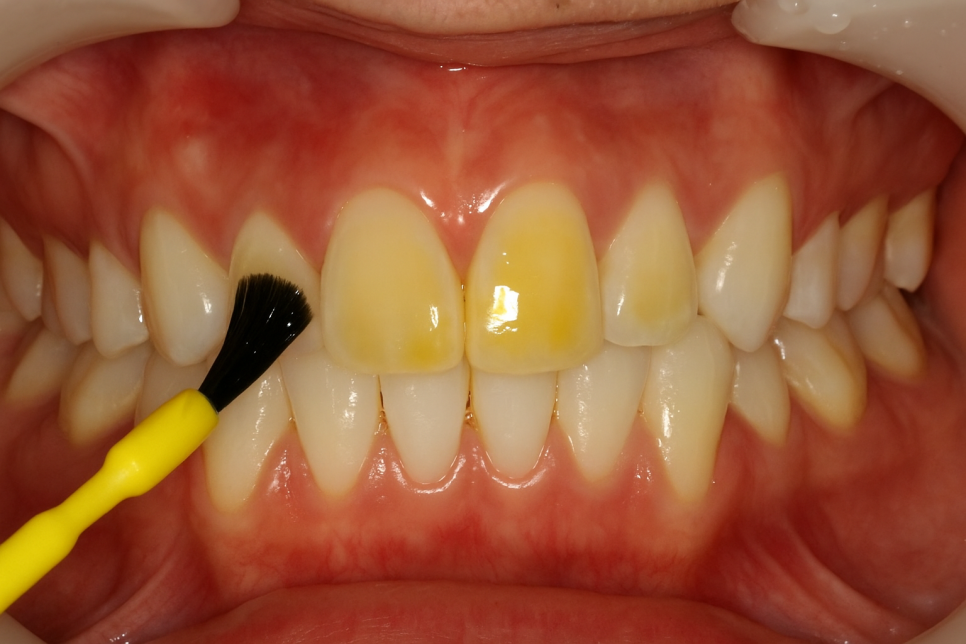

필요시에는 불소를 도포하여 어린이 충치를 예방하고,

보건 교육을 통해 양치질 같은 습관을 개선하고,

치면 세마를 통해 치태나 치석을 제거합니다.

이러한 관리를 수혜 받을 때 경제적인 부담을 덜 수 있도록

불소도포, 보건교육, 치면 세마를 진행해도

본인 부담금은 10%만 청구됩니다.